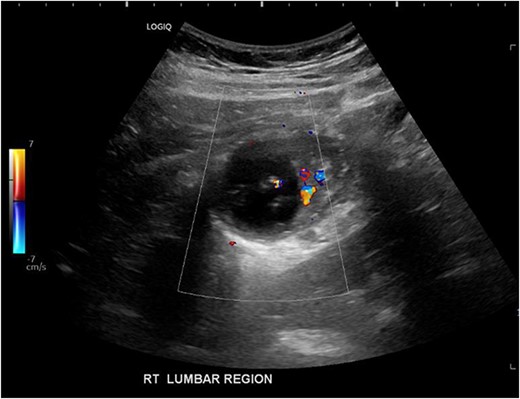

His white cell count was 12.7 × 109/L (reference range 3.7–9.5 × 109/L) and c-reactive protein was 39 mg/L (reference range ≤ 4 mg/L). Hydatid and entamoeba serologies were negative. Carcinoembryonic antigen was elevated to 11.4 ug/L (reference range ≤ 3 ug/L). Abdominal ultrasound showed an uncharacterizable RLQ cystic structure with calcification (Fig. 1). Subsequent computed tomography (CT) scan demonstrated a 56 mm × 43 mm × 58 mm ovoid ascending colon mass with central low density and rim enhancement (Fig. 2). Ileocolic lymphadenopathy up to 7.5 mm in diameter was noted with no evidence of distant metastatic disease.

Ultrasound image demonstrating a cystic lesion with internal calcification and no hypervascularity.

Diagnosis of colonic duplication cyst is reliant on radiology, intra-operative findings and histopathology. The typical finding on ultrasonography (US) is a cystic lesion with hypoechoic outer rim representing the smooth muscle layer [3, 7]. Endoscopic US may additionally demonstrate submucosa and mucosa as inner hyperechoic layers [3, 7]. CT typically demonstrates a fluid filled cystic lesion or a thin walled tubular structure. As in this case, a CT scan with oral contrast may be utilized to evaluate for bowel obstruction.